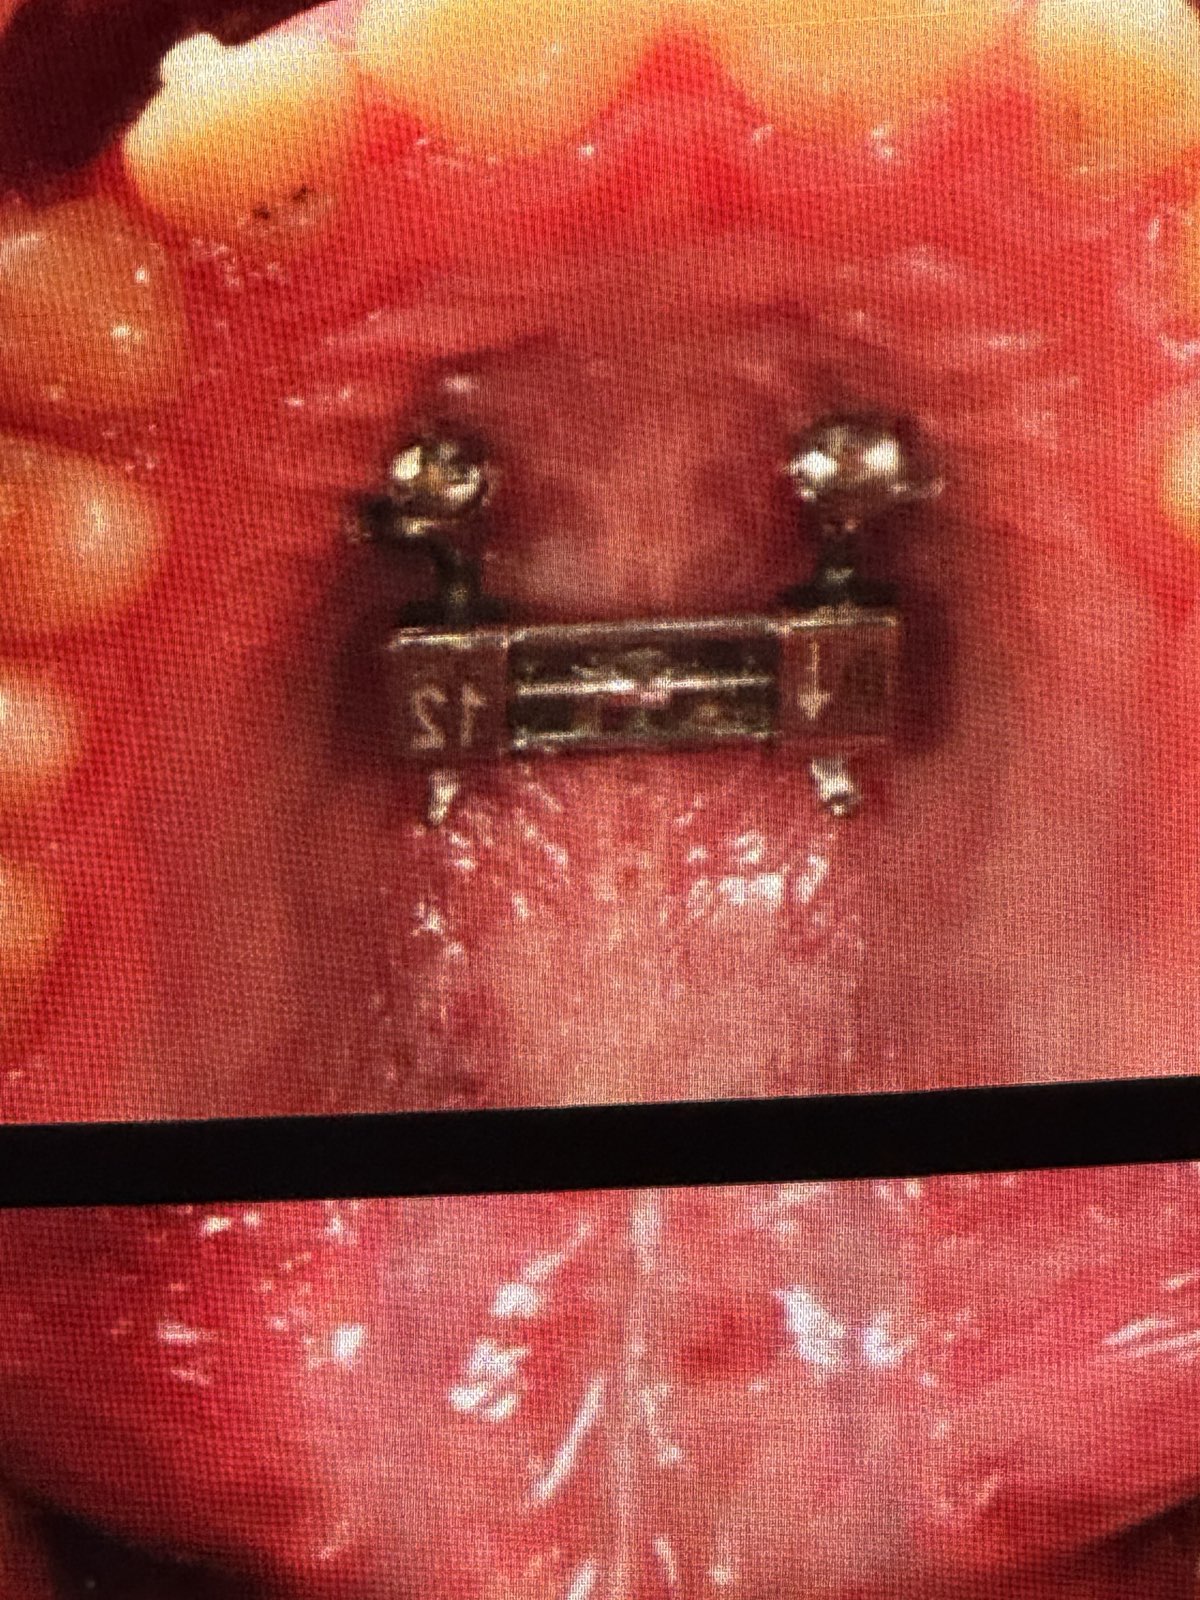

• MARPE(上顎急速拡大装置)に関する言及

• 重度横幅狭窄のある成人患者には、パワーネジ(Power Screw, ドイツTiger社製)のような強力なスクリューと、必要に応じて骨切り手術(ピエゾサージェリーシステムによる単純な手術)を併用したMARPEを適用する。

• 骨切り手術: 口蓋側のmaxillaに2つの小さな切開を入れ、ピエゾサージェリーの角度付きチップで縫合線を破断。切歯間にも切開を入れる。

• 効果: MARPEは骨格性の拡大を可能にし、歯の傾斜を防ぎ、成人における難症例の拡大をより予測可能にする。

• Tippingの制御: アライナーのずれを防ぐため、長方形の水平アタッチメントを配置することが有効。